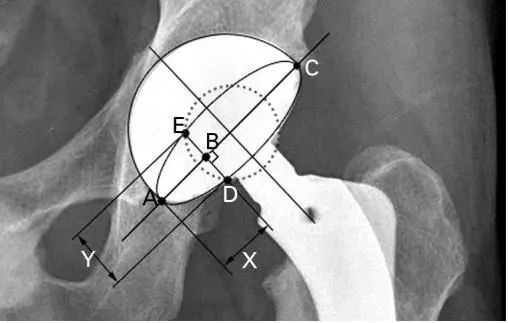

6.Ackland, Bourne and Uhthoff’s method:a是臼杯长轴(AC)的距离,x是沿AC线的距离(AB)。在与直径成直角的位置上画一个任意的切线,y是沿这个切线(DE)到两个杯缘的距离(图7)。

(图6)

7.Hassan’s method :其中D为椭圆的最大直径。任意的切线与直径成直角。这条切线在直径线和杯子边缘之间的距离是y/2(图7)。X是从椭圆的末端到切线和直径线之间的截面的距离

8.Ackland’s method:在椭圆的直径中心画一个直角(图7),到臼杯边缘的交点的距离是b/2。任意的切线与直径成直角。沿切线到两个杯形边缘的距离是y。X是从椭圆的末端到切线和直径线之间的横截面的距离

(图7)